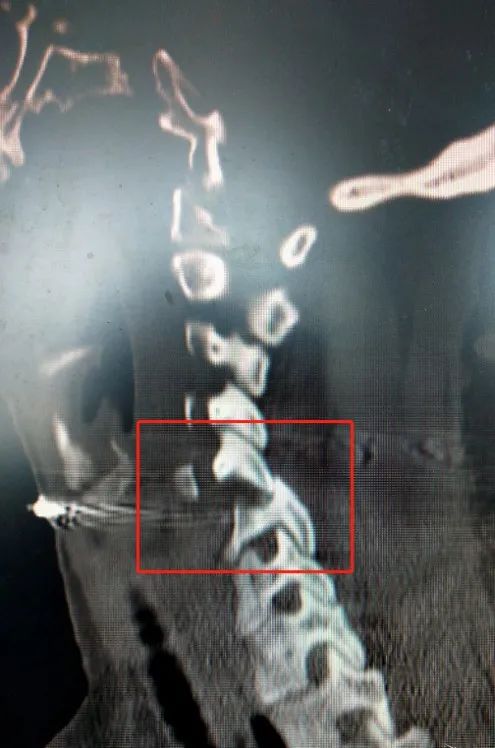

最常见的情况之一是脊柱后脱位。

面部、前额和脸颊遭受暴力和意外时,可能会导致脊柱过度拉伸。一旦暴力超过了颈前肌肉群体和前纵韧带的张力,脊柱就会过度拉伸。

此时,身体处于相对稳定的状态,颈部七个椎体以下的部位不会随着颈椎的活动而移动,因此就会在脊柱上形成水平切力,导致韧带撕裂,情况更为严重时,就会发生脊椎后脱位现象。